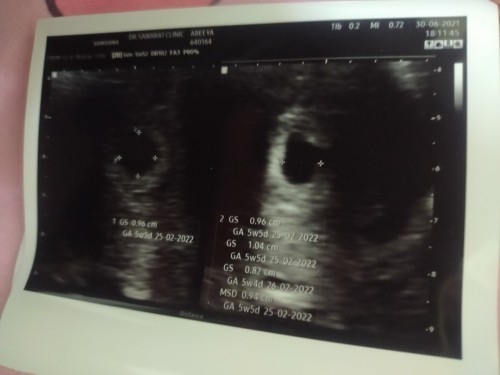

5w กังวลอยู่เหมือนกันค่ะ รอนัดซาวอีกครั้งเมื่อครบ 12w ค่ะว่าจะเจอมั้ย